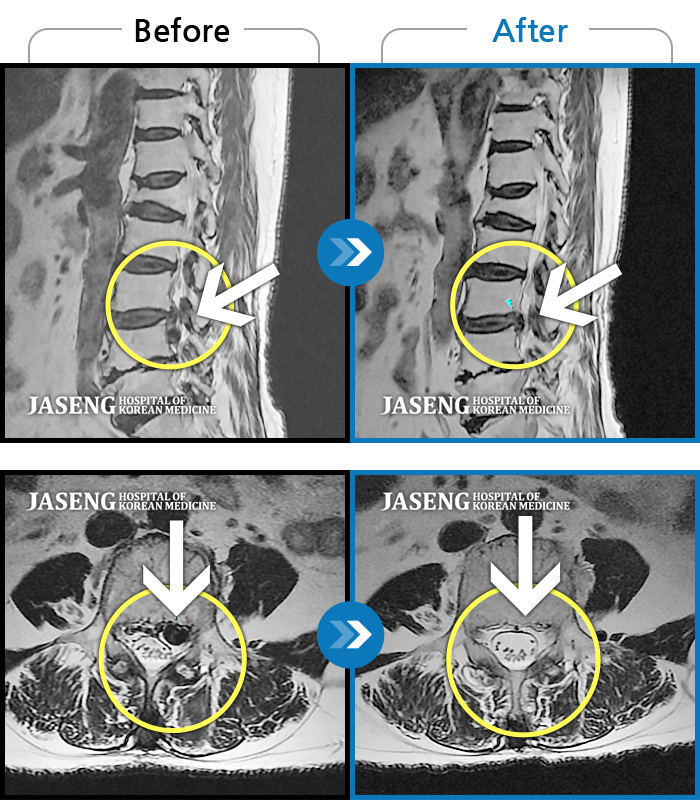

허리디스크

보라매 · 왕오호 원장

좌측 허리 통증 및 좌측 다리 저림

촬영시기

2016.05.21 ~ 2018.04.13

2018.12.28